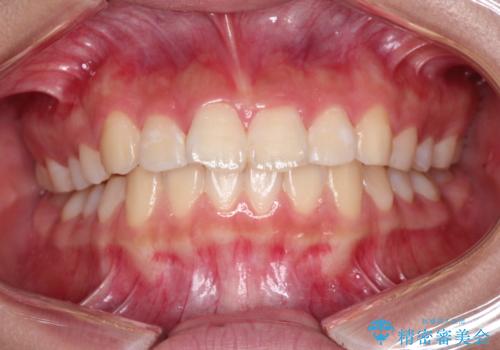

インビザラインによる出っ歯の非抜歯矯正

- 前歯が出ているのを主訴に来院されました。

上の前歯が前方に傾斜しており、上の前歯と下の前歯が接触していない状態でした。

上の奥歯を後方に移動させて、前歯を引っ込める計画としました。

しっかり使っていただけたので、スムーズに治療を終了することができました。